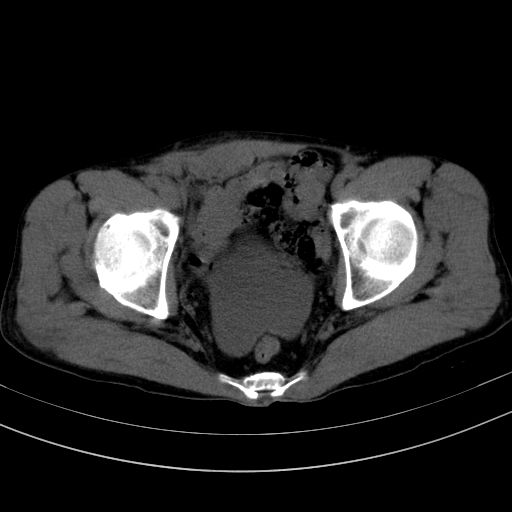

以下是引用37度在2010-1-9 14:37:00的发言:[br]1.双肾囊肿,左肾积水结石,.胆总管轻度扩张;[br]2.病灶在腹膜外,考虑纤维瘤。

以下是引用dyqct在2010-1-9 17:56:00的发言:[br]考虑:1.双肾囊肿,左肾积水结石、旋转不良。[br] 2.右侧腹直肌血肿或纤维瘤。[br]肠道准备不好。做个增强。